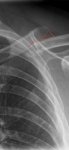

Esto que marco con dos puntos rojos si ampliáis son trozos de hueso rotos y sueltos?

Alguien me puede aconsejar un cabestrillo que sea cómodo de verdad en la zona del cuello que soporta el peso del brazo?.

Sí, son dos astillas. Puede haber más, visto desde atrás o desde arriba. Las fracturas irregulares tienen formas que no se aprecian bien con una RX frontal.

Lo que puse no es rx,esa es la primera foto del tac y después vienen muchísimas más en todos los planos.

Pero es la única que se ver los trocitos..

mal de la rx es la que se ve el desplazamiento porque me la hicieron de pie…

En cuanto me tumbo cómo en el tac se alinea…